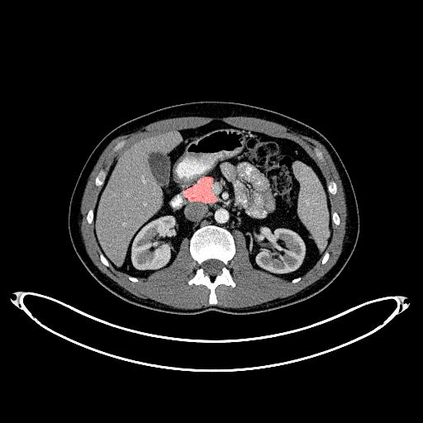

In this paper, we adopt 3D Convolutional Neural Networks to segment volumetric medical images. Although deep neural networks have been proven to be very effective on many 2D vision tasks, it is still challenging to apply them to 3D tasks due to the limited amount of annotated 3D data and limited computational resources. We propose a novel 3D-based coarse-to-fine framework to effectively and efficiently tackle these challenges. The proposed 3D-based framework outperforms the 2D counterpart to a large margin since it can leverage the rich spatial infor- mation along all three axes. We conduct experiments on two datasets which include healthy and pathological pancreases respectively, and achieve the current state-of-the-art in terms of Dice-S{\o}rensen Coefficient (DSC). On the NIH pancreas segmentation dataset, we outperform the previous best by an average of over 2%, and the worst case is improved by 7% to reach almost 70%, which indicates the reliability of our framework in clinical applications.